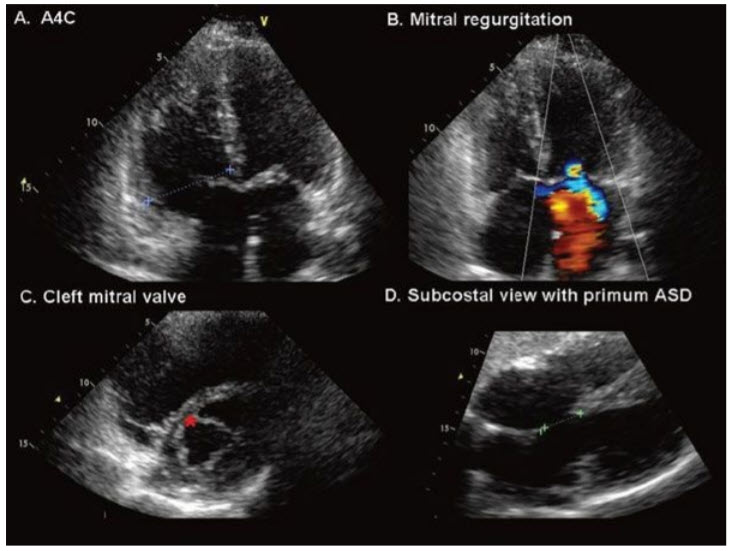

A secundum ASD is the common type of ASD and is located centrally in the interatrial septum at the site of the fossa ovalis. The defect may be single, multiple, or fenestrated. This defect is best viewed by transthoracic echocardiography in the subcostal view (due to ultrasound waves being better reflected off the interatrial septum in this view). Coexisting partial anomalous pulmonary venous drainage is seen in 5% of patients with a secundum ASD. The atrial septal defect occurs when the interatrial septum is deficient at the crux of the heart/level of the atrioventricular valves. A primum ASD occurs as part of the spectrum of AVSD. Partial AVSD commonly describes a primum ASD in combination with a so-called cleft mitral valve, more correctly described as a trileaflet left-sided AV valve. Primum ASDs are often well demonstrated from the apical four-chamber view (± subcostal) in association with mitral regurgitation from a trileaflet left-sided AV valve (figure below).

Primum ASD and its associated features. Note that the septal leaflet of the tricuspid valve is on the same plane as the mitral valve (A). Normally the septal leaflet of the tricuspid leaflet is apically displaced compared with the mitral valve. Mitral regurgitation frequently coexists with primum (B). (C) Short-axis views of the mitral valve show a “cleft” pointing toward the septum (*). (D) The cleft is more accurately characterized as a commissure between the superior and inferior bridging leaflets of the common AV canal. Additional echocardiographic features of AVSD (not demonstrated here) include elongation of the LV outflow tract (gooseneck deformity) ± LVOT obstruction. A4C, apical 4 chamber; ASD, atrial septal defect.